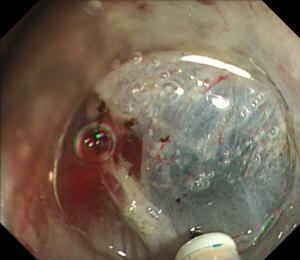

| 【胃ESD】 |

粘膜下層剥離術専用の電気メスを用いて早期胃癌のすぐ下の層(粘膜下層)を剥離します。 |

粘膜下層の剥離が進んで早期胃癌が存在する表面の部分(粘膜)が剥がれてきました。 |